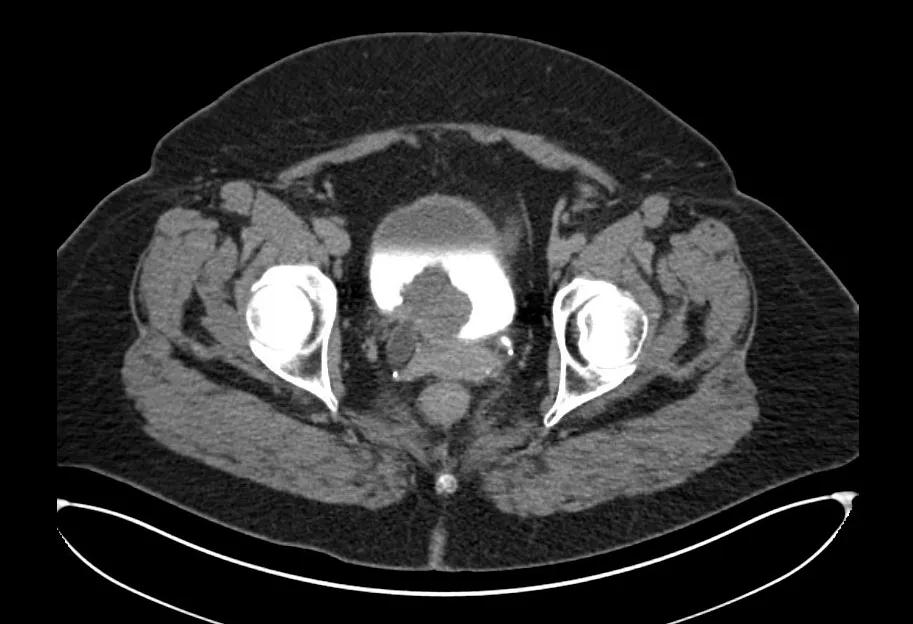

CT scan of female patient bladder cancer

In muscle-invasive bladder cancer, interim imaging during neoadjuvant chemotherapy may help identify those who are not likely to respond to treatment, preserving their candidacy for a vaginal-sparing approach. So conclude the authors of a retrospective study, published in Urology.